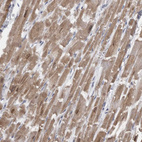

Immunohistochemical staining of human cerebellum shows moderate cytoplasmic positivity in Purkinje cells.